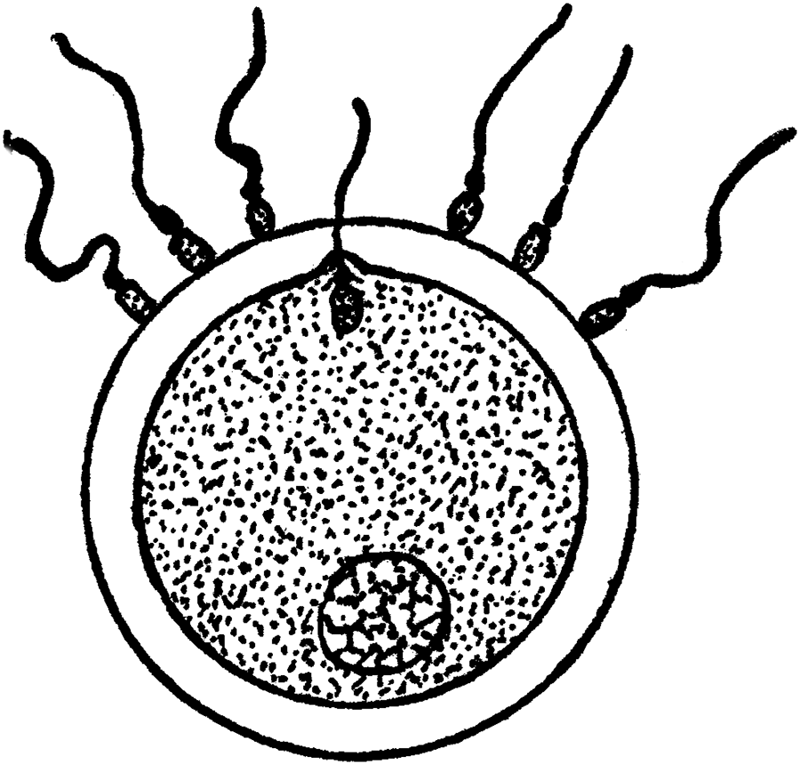

The Ovaries. The ovaries are the essential organs of reproduction. For it is they that generate the eggs, or ova, or ovules, which, after becoming fertilized or fecundated by the spermatozoa of the male, develop into children. Without the ovaries of the female, the same as without the testicles of the male (to which they correspond), no children could be begotten, and the entire human race would quickly disappear from our planet. The ovaries are two in number; they are embedded in the broad ligaments [35]which support the womb in the pelvis, one on each side of the womb. They are of a grayish or whitish pink color, and are about an inch and a half long, three-quarters of an inch wide, and one-third of an inch thick. They weigh from one-eighth to one-quarter of an ounce. Their surface is either smooth or rough and puckered. Think of a large blanched almond and you will have a pretty fair idea of the size and shape of an ovary.

Ovary.

Number of Ova. When the female infant is born, her ovaries contain as many ova or eggs as they ever will contain. In fact, they contain more than they will at puberty. For it is estimated that at birth each ovary contains about 100,000 ova; the majority of these, however, disappear so that at the age of puberty each ovary contains only about 30,000 ova. As only one ovum ripens each month from the time of puberty to the time of the menopause (i.e., about 300 to 400 ova at the utmost during [52]a lifetime), and as only a dozen or two ova would be necessary for the propagation of the race, it seems a superabundance of ova, an unnecessary lavishness. But nature is lavish where the propagation of the species is concerned. A portion of an ovary or of both ovaries might become diseased, and thousands of ova might become unfit for fertilization; nature therefore puts in an extra reserve supply. We see a still more striking example of this extreme extravagant lavishness in man; only one spermatozoön is necessary to impregnate the ovum, and only one spermatozoön can penetrate the ovum; nevertheless each normal ejaculation of semen contains between a quarter and half a million spermatozoa.

The Graafian Follicles. Each primitive or primordial ovum[3] is imbedded in a little vesicle or follicle, which is generally known as Graafian follicle, and there are as many Graafian follicles as there are ova. (The Graafian follicles were first described about 250 years ago—in 1672—by a Delft physician named De Graaf, hence the name.) Until puberty, that is the commencement of menstruation, the Graafian follicles with the oöcytes or primitive [53]ova are in a more or less dormant condition. But with the onset of puberty there commences a period of intense activity in the ovaries. This period of activity is repeated regularly once a month, and it constitutes the process of ovulation and menstruation. The two processes are closely though not causally connected. Ovulation consists in the monthly maturation and extrusion of a ripe ovum; menstruation, which will be further discussed in a separate chapter, consists in the monthly discharge of blood, mixed with mucus from the inside lining of the uterus. Every twenty-eight days, from the [54]time of puberty to the time of the menopause, a Graafian follicle bursts and an ovum is extruded from the ovary. Before the follicle bursts, it swells and enlarges and reaches the surface of the ovary; the whole follicle is congested with blood, but at one point near the surface of the ovary it is pale and thin, and here the rupture takes place.

Section of Ovary.

1. Graafian follicle in the earliest stage.

2, 3, 4. Follicles in more

advanced stages.

5, 7. Almost mature follicle.

6. Follicle from which

the ovum has escaped.

8. Corpus luteum.